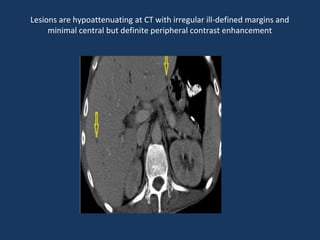

Lesions are hypoattenuating at CT with irregular ill-defined margins and

minimal central but definite peripheral contrast enhancement

Lesions are hypoattenuatingat CT with irregular ill-defined margins and minimal central but definite peripheral contrast enhancement